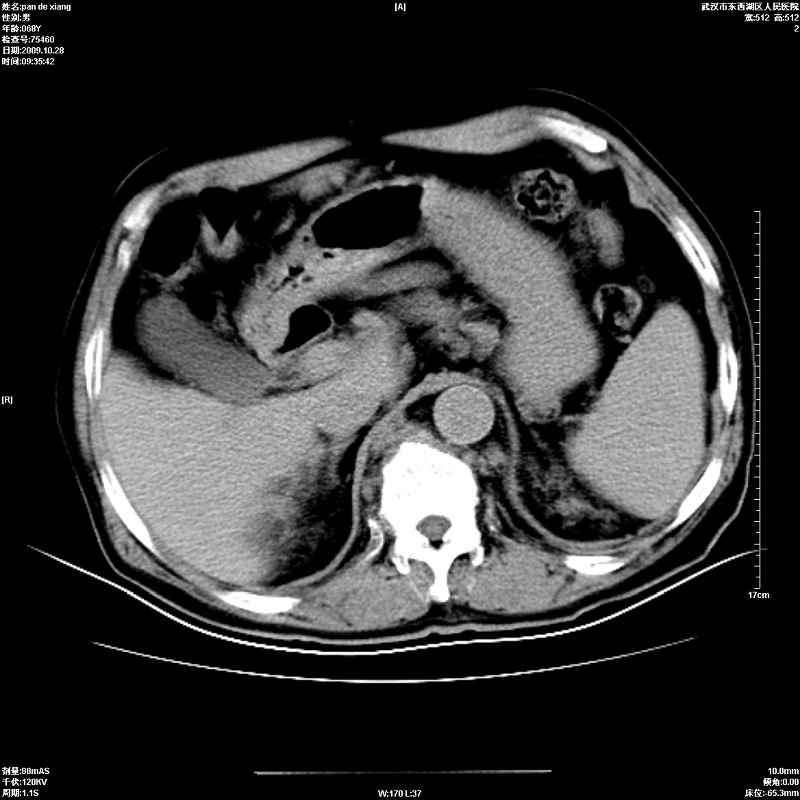

以下是引用杀毒软件在2009-10-28 20:41:00的发言:[br]结合临床考虑---白血病双肾改变或淋巴瘤。

以下是引用zxl51642在2009-10-29 9:59:00的发言:[br]结合临床“单克隆免疫球蛋白血症”,考虑双肾为继发损害并肾功能不全(尿中大量igg及少量iga、igm等大分子免疫球蛋白滤出所致继发损害),椎前软组织肿块为髓外造血。与浆细胞瘤有区别,平扫时有战友说的很清楚。